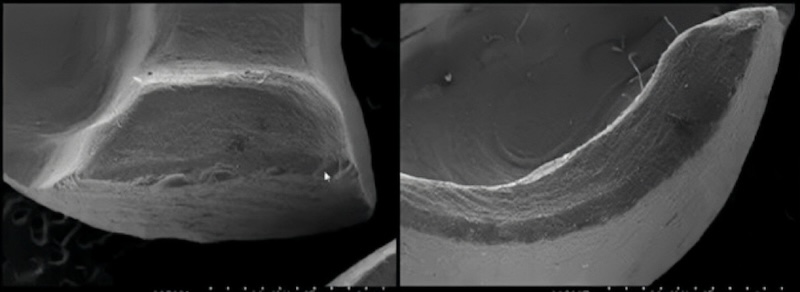

| 強度 | 強度較弱的陶瓷,約160 MPa |

| 使用區域 | 長石陶瓷主要用在前牙(美觀區),不適合用在大臼齒。能和牙齒形成強而有力的連結(bonding),在琺瑯質保存的狀況下,有很好的加強效果 |

| 優點 | 外觀最自然、能做非常薄、磨牙量最少;對光線的反射最接近真牙 |

| 缺點 | 抗咬力與耐用性最低;若厚度太薄或黏著不良,容易破裂或脫落 |

| 強度 | 300–600 MPa |

| 使用區域 | 抗彎強度比長石優秀,可承受前牙咬合壓力,也常運用於後牙、大臼齒的修復。除了常見的 e.max,也不斷有新的加強款如 Tessera 等陶瓷問世 |

| 優點 | 良好強度與透光性的平衡;外觀漂亮;相對破裂風險低於長石;技術成熟 |

| 缺點 | 價格比長石高;對製作精度與黏著技術要求仍高;在極高咬合力或磨牙者可能也會破損 |

| 強度 | 900–1200 MPa(陶瓷界的大力士) |

| 使用區域 | 無論前牙、後牙都可以使用。如果有嚴重磨牙的狀況,就會優先考慮氧化鋯 |

| 優點 | 非常耐用、耐磨、耐崩邊;適合後牙或咬合力大者 |

| 缺點 | 若表面沒有高度拋光,長期下來對於對咬牙的傷害很大!透光性與自然感較弱;若設計不良可能外觀偏「假」或顏色死白;和自然牙的連結較弱 |